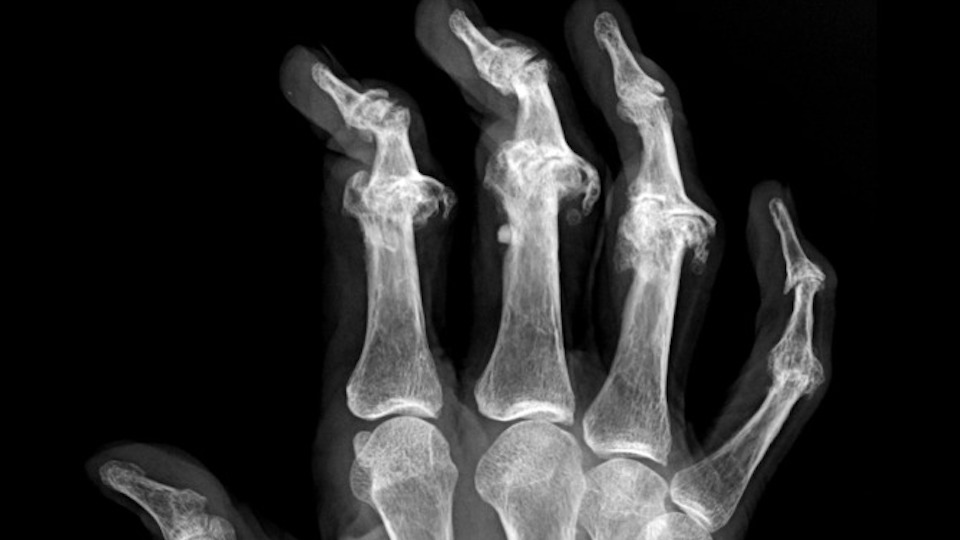

Psoriatic Arthritis Up to 30 percent of people with psoriasis develop psoriatic arthritis, an inflammatory form of arthritis. Psoriatic arthritis can cause swelling, stiffness and pain in and around the joints, cause nail changes and overall fatigue. Studies show that delaying treatment for psoriatic arthritis as little as six months can result in permanent joint damage. […]